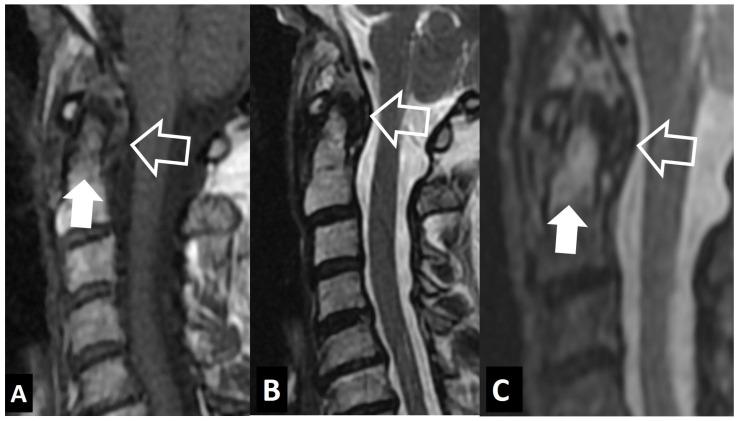

A series of conditions can mimic musculoskeletal infections on imaging, complicating their diagnosis and affecting the treatment. Depending on the anatomical location, different conditions can manifest with clinical and imaging findings that mimic infections. Herein we present a wide spectrum of the musculoskeletal disorders of the axial skeleton, long bones, peripheral joints, and soft tissue that may manifest as infectious processes, and we focus on the potential mimics of osteomyelitis, septic arthritis, and infectious spondylodiscitis that are common in clinical practice. We present the typical imaging characteristics of each musculoskeletal infection, followed by mimicking conditions.

一系列病症在影像学上可模拟肌肉骨骼感染,使诊断复杂化并影响治疗。根据解剖位置的不同,不同病症可表现出类似感染的临床和影像学表现。在此,我们展示了轴向骨骼、长骨、外周关节和软组织的广泛肌肉骨骼疾病,这些疾病可能表现为感染过程,并且我们重点关注临床实践中常见的骨髓炎、化脓性关节炎和感染性脊椎间盘炎的潜在模仿病症。我们介绍了每种肌肉骨骼感染的典型影像学特征,随后是模仿病症。